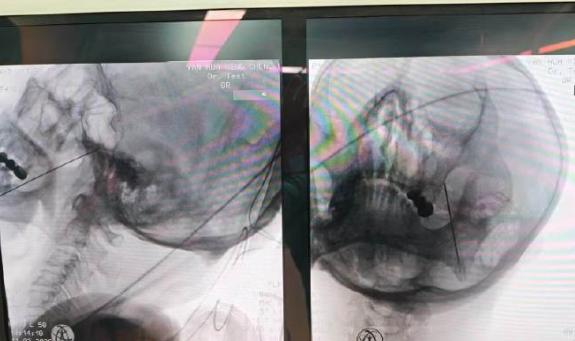

到院检查后,医生确诊为带状疱疹后三叉神经痛,为老人实施了三叉神经半月节射频治疗。治疗后,困扰老人许久的疼痛明显缓解,吃饭、睡觉都恢复了正常,终于摆脱了“天下第一痛”的折磨。

三叉神经半月节射频是目前治疗这类三叉神经痛的优选方式,全程在C臂/CT精准引导下进行,用极细的射频针直达疼痛“总开关”,温和调节受损神经,阻断痛觉信号。